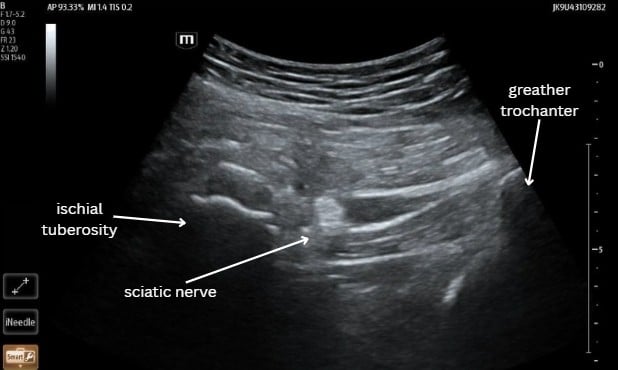

Ultrasound-guided Transgluteal Sciatic Nerve Hydrodissection (TSNH) is a similar procedure wherein D5W or a similarly inactive fluid is used to decompress the sciatic nerve. [Figure 1] This procedure causes mechanical decompression and does not cause motor blockade; it is therefore useful in the ED as patients are ambulatory after the procedure and can be safely discharged with their pain controlled. Here we present a case of a patient in the ED presenting with sciatic pain treated with this procedure.

A 61-year-old male presented to the ED complaining of 2 weeks of persistent worsening right-sided back pain radiating down his right leg to his foot. He also reported numbness to his medial calf and difficulty ambulating with a walker. Pain was unrelieved by tylenol, ibuprofen, or muscle relaxants. Consent for a TSNH was obtained and the procedure was performed under ultrasound guidance using sterile technique with a 20 gauge echogenic nerve block needle. 20mL of D5W was used for hydrodissection. The patient was placed in lateral recumbent position and the anatomy was identified. [Figure 1] The needle was visualized using a longitudinal approach and D5W was deposited around the sciatic nerve. [Video 1] The patient reported improvement in his pain scale from a 10 to a 4, became ambulatory, and was discharged an hour later without complications.